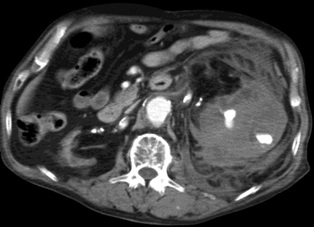

超选择胃十二指肠动脉显示出血的动脉来自于胃十二指肠动脉的一个细小的未命名动脉分支 |